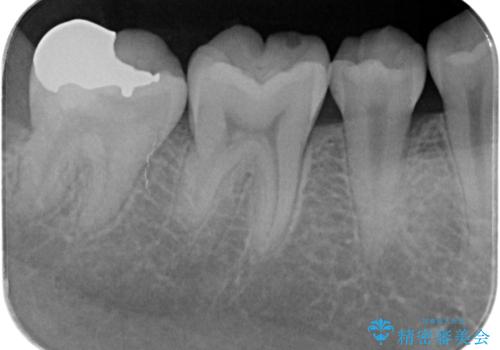

- 検査の結果虫歯が見つかった患者様です。

親知らずを抜歯してから虫歯を除去した後、ゴールドの詰め物で修復します。

比較的大きな虫歯でしたがゴールドでの修復にすることで歯の削る量を抑え、精度の高い治療を行うことができました。